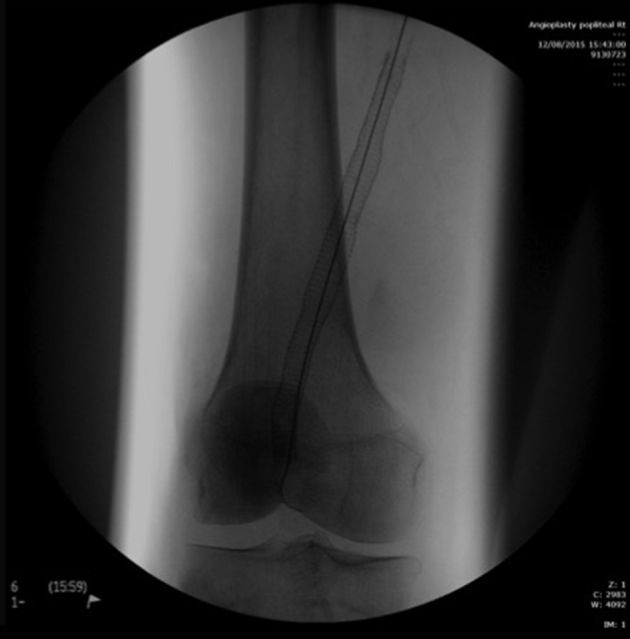

Figure 3.

On-table imaging showing deployed stent.